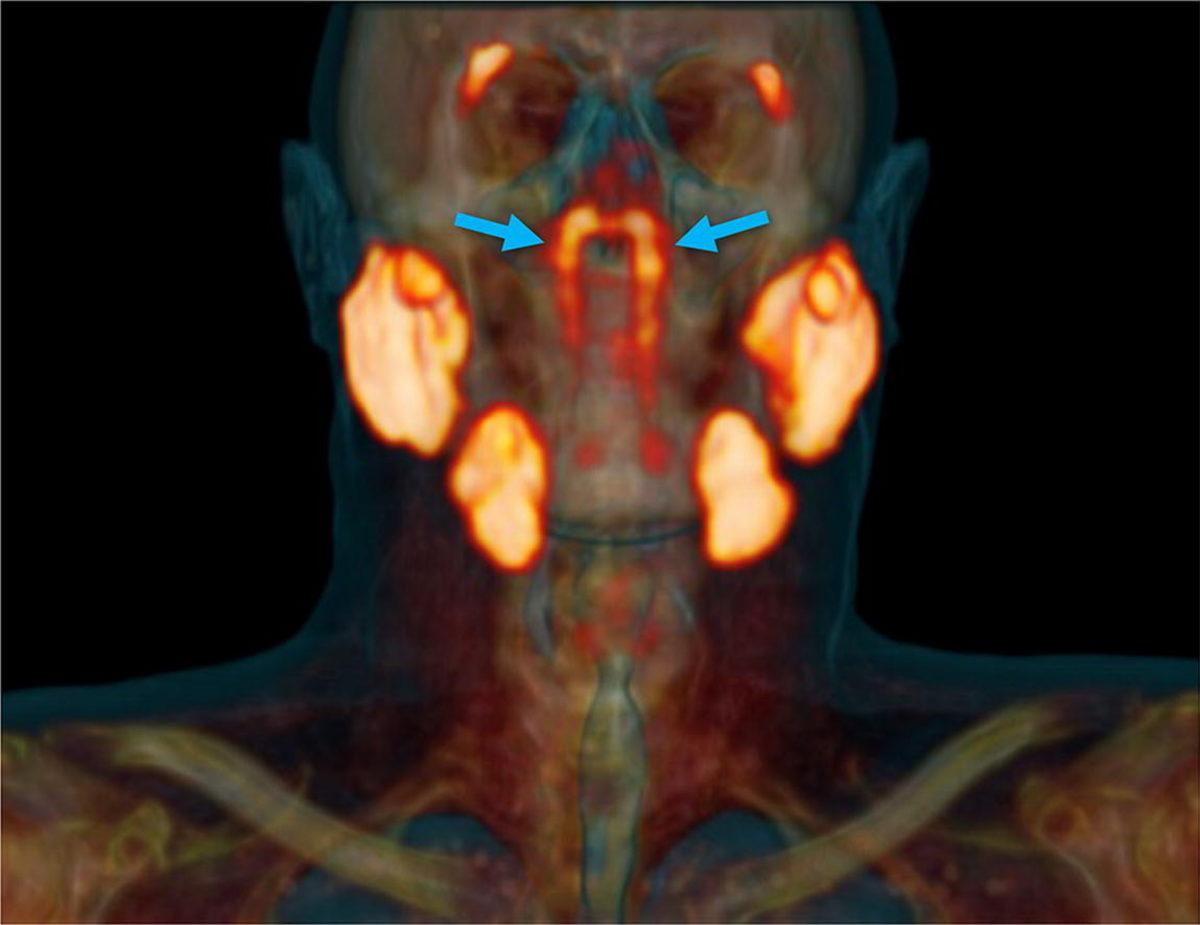

Söz konusu yeni organı keşfeden bilim insanları, torus tubarius adı verilen bir kıkırdak parçası üzerinde bulunduğu için yeni tükürük bezine tubarial tükürük bezleri adını verdi. Bilim insanlarının tahminlerine göre söz konusu tükürük bezleri, burun ve ağzımızın arkasında kalan üst boğaz bölümünü nemlendirmekten sorumlu.

Yapılan açıklamalara göre keşif, bir tesadüf sonucu gerçekleşti. Hollanda Kanser Enstitüsü'nde çalışmalarına devam eden bilim insanları, prostat kanserini incelemek için BT taramaları ve PSMA PET-CT adı verilen pozitron emisyon tomografisi (PET) taramalarının bir kombinasyonunu kullanıyorlardı. PSMA PET-CT taraması, yalnızca metastatik prostat kanserini tespit etmede geleneksel görüntülemeden daha iyi olmakla kalmıyor, tükrük bezi dokusunu tespit etmede de oldukça iyi sonuçlar veriyor ve keşif de bu taramalar sırasında gerçekleşti.